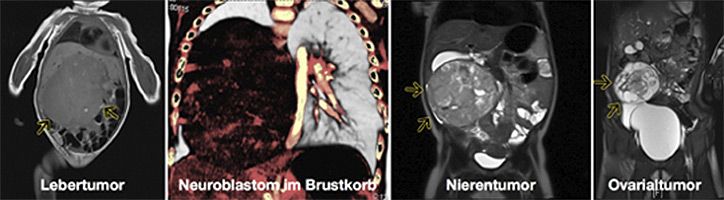

Operationen von soliden kindlichen Tumoren, die außerhalb des Schädels und des zentralen Nervensystems liegen, stellen einen Schwerpunkt der klinischen und wissenschaftlichen Arbeit unserer Abteilung dar.

Die Kinderchirurgie repräsentiert innerhalb der Gesellschaft für Pädiatrische Hämatologie und Onkologie (GPOH) und zahlreichen internationalen Studiengruppen (SIOPEL, RTSG, CWS und SIOPEN) ein referenzchirurgisches Zentrum für Nieren-, Leber- und Weichteiltumore. Sie ist ein ausgewiesenes Referenzzentrum für kindliche Neuroblastome und seltene Tumoren im Kindesalter. Pro Jahr werden in der unserer Abteilung zwischen 120 und 150 Kindern mit soliden Tumoren operiert.

Im Besonderen werden viele innovative chirurgische Verfahren in enger Kooperation mit der Klinik für Allgemein, Viszeral – und Transplantationschirurgie, der Klinik für Herz-Thorax- und Gefäßchirurgie, Klinik für plastische Chirurgie und Klinik für Neurochirurgie angeboten. Dazu zählen Organtransplantationen, Operationen an der Herz-Lungenmaschine bei ausgeprägten Tumorthrombosen der großen Gefäße, Neuromonitoring, Nervenersatz und freie Hautlappentechniken bei Weichteilsarkomen, die HIPEC,  Brachytherapie und CT gestützte Markierung von Lungenmetastasen.